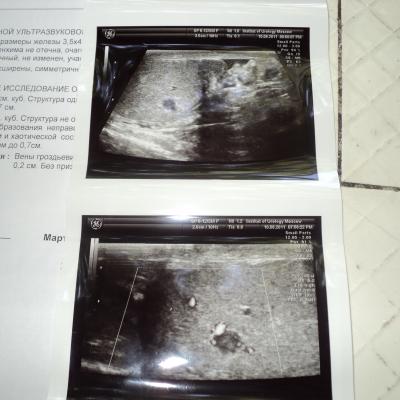

Здравствуйте! Сделал Узи мошонки с допплером: Правое яичко: Объемом 6,0 см.куб. Структура однородная.придаток не увеличен. Головка придатка размером до 0,7 см. Левое яичко: Объемом 6,0 см. куб. Структура не однородная за счет наличия в среднем сегменте гипоэхогенного образования неправильной формы до 0,7 см. с умеренно выраженным кровоснабжением и хаотической сосудистой архитектоникой . Придаток не увеличен. Головка придатка размером до 0,7 см. Вены гроздьевидного сплетения слева при натуживании расширены до 0,2 см. Без признаков ретроградного кровотока.Сдал анализ крови на АПФ(МЕ/мл) результат 3,норма меньше 8. Бета ХГЧ (МЕ/л)-результат 0,норма от 0-8. ЛДГ результат 316,норма от 0-450. Пожалуйста скажите,что это такое? Я очень переживаю!!!